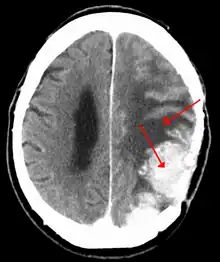

| An MRI of the brain, demonstrating the appearance of a meningioma | |

Meningiomas are visualized readily with contrast CT, MRI with gadolinium,[23] and arteriography, all attributed to the fact that meningiomas are extra-axial and vascularized. CSF protein levels are usually found to be elevated when lumbar puncture is used to obtain spinal fluid. On T1-weighted contrast-enhanced MRI, they may show a typical dural tail sign absent in some rare forms of meningiomas.[18]